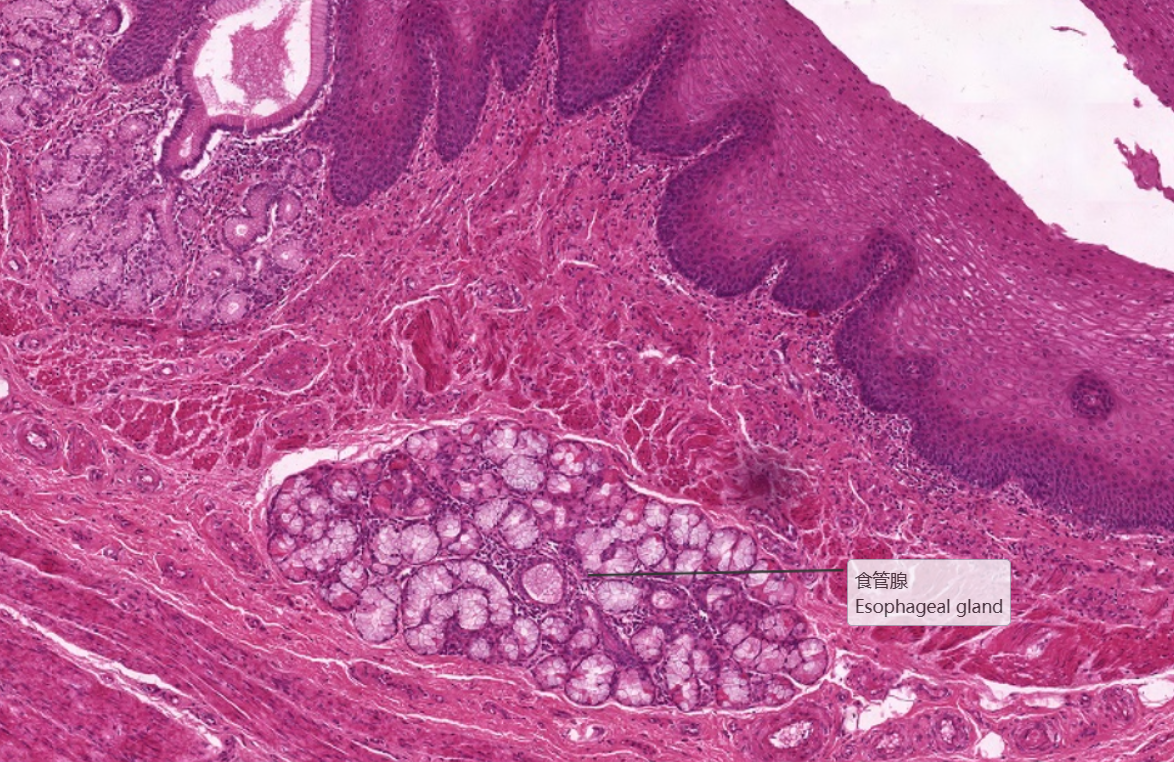

在食管横断面上肌细胞呈横断面。2、 黏膜下层:为疏松结缔组织,呈粉红色,纤维比较粗大,除细胞外,

还有较大的血管。此外,此层可见有黏液性的复管泡状的食管腺。3、 肌层:该片取自食管上三分之一部分,

4.食管腺